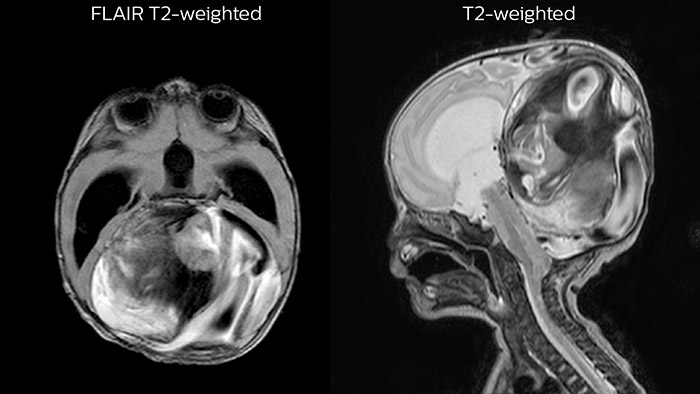

Dural sinus malformation (DSM) Initial examination

After three times of coiling and acryl based embolization

Hydrocephalus post hemorrhagic Both pictures show a ventriculoperitoneal shunt. With our previous scanner our hydrocephalus protocol needed about 25 min. With Ambition the examination time is about 14 min. including a CSF PCA sequence to show flow in the aqueduct.